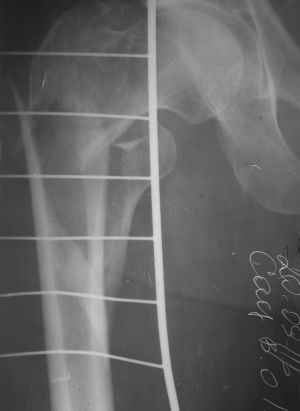

Чрезвертельный перелом правого бедра

Пациент 64 лет, поступил к нам 20.09.11. Сбит автомобилем. Сейчас на скелетном вытяжении. На КТ видно раздробленность черезвертельной зоны в саггитальной плоскости и вовлеченность шейки. Гамма? LCP?

В чем сомнения? Перелом распространяется на диафиз, так что оптимально - длинный проксимальный гвоздь, 3 разреза по 1,5-2 см, операция 20-30 мин. DHS или другие пластины менее предпочтительны. То, что область вертела имеет какие-то линии раскола, с гвоздем не имеет никакого значения. Нужно зафиксировать проксимальный фрагмент (головка-шейка) к диафизу в правильных взаимоотношениях, неважно, что там между ними.

Приветствую,коллеги.Учитывая подвертельную распространённость зоны перелома, имеются все показания для интрамедуллярной конструкции. DHS в данном случае работать не будет, как вариант возможно использовать DCS или клинковую пластину 95 градусов.